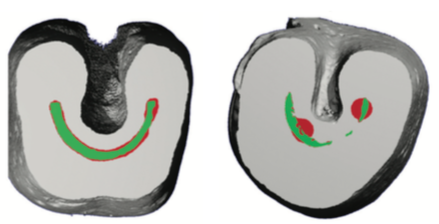

下の写真は歯の根っこの横の断面図です。左側のような円形に近い単純な根管の形態では特に問題になるようなことは少ないですが、右のような円形ではない複雑な形態の根管に関しては大きく差が出てしまいます。

SAFでは、しっかりと形成し清潔にすることができますが、従来の器具では大幅に取り残してしまい清潔にすることはできません。

樋状根や扁平型をした根管には特に効果的です。

左がSAFを用いて治療したもの。

右が従来型の器具を用いて治療したもの。

緑色の部分が本来の根管の形。

赤くなっているところが、しっかり形成できているところです。

左は、満遍なく過不足なく全体を形成できています。

右は、必要な部分は触れずに、必要以上に円形に不必要な部位を削っていますし、必要なところは形成できていません。